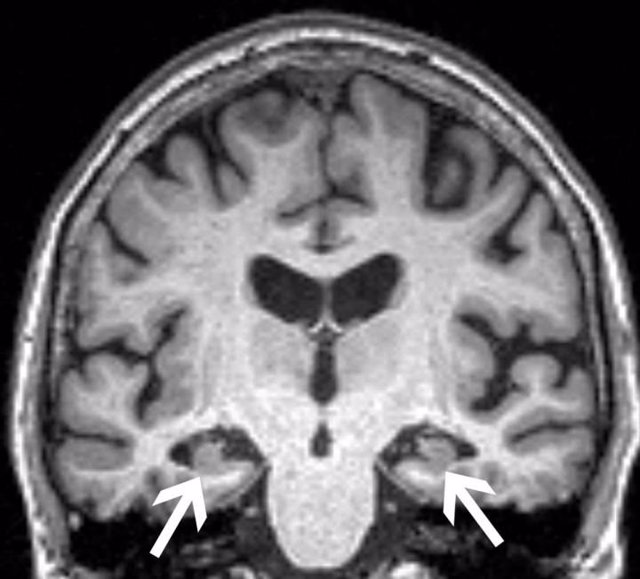

Engineer Team : RESONANCIA MAGNETICA Magnetic Resonance Imaging – Clinical Images Hallazgos por resonancia magnética cerebral de nuestro paciente. M, 21 … Imágenes por resonancia magnética anormales como predictoras de mal … Imágenes por resonancia magnética anormales como predictoras de mal … Lesiones en resonancia magnética (RM) del encéfalo y la médula espinal … Pin en Resonancia Magnética del Encéfalo A) Resonancia magnética cerebral (RMC) mostrando infartos en … Caso 1: Edema cerebral visualizado mediante RM. (A) Secuencia T1 plano … Rascacielos dormir pasta tac y resonancia diferencias retrasar … Pin on Apuntes de Enfermería y T.C.A.E Resonancia magnética cerebral secuencia T2, que muestra lesión … Meningitis aguda en la enfermedad de Behçet | Reumatología Clínica Resonancia magnética coronal normal del cerebro Fotografía de stock – Alamy Imágenes de resonancia magnética, la imagen de la cabeza en diferentes … Resonancia magnética cerebral A) protocolo T1 sagital (Caso 1). Se … Resonancia magnética cerebral. Secuencia T1 corte sagital. Atrofia … Resonancia magnética de cerebro, cortes axiales, secuencias T2. Señal … Resonancia magnética de cráneo. A y B) Cortes axiales FLAIR … Resonancia magnética (RM) de cerebro, corte axial ponderado en T2: la … RM cerebral: Interpretación paso a paso | Kenhub Resonancia magnética de cerebro, cortes axiales, secuencias T2. Señal … De Resonancia Magnética De Cerebro Foto de archivo – Imagen de arteria … Top 107+ Imagenes de resonancia cerebral normal – Destinomexico.mx -Imagen por resonancia magnética del cerebro. a) Cortes sagital y axial … resonanCia magnétiCa Cerebral donde se observa hiperintensidad a nivel … MRI (Imagen de resonancia magnética) – Tomografía computarizada de la … Meningioma – NCI Imágenes por resonancia magnética coloreadas del cerebro sano del … Resonancia magnética cerebral en secuencia FLAIR, que muestra lesiones … Contraste resonancia magnetica cerebral – senturinthegreen Relación de los espacios de Virchow-Robin con la enfermedad de … Gliomatosis cerebral – Instituto Nacional del Cáncer Pin en Neurology. Recomendaciones para la utilización e interpretación de los estudios de … Fotografía De La Proyección De Imagen De Resonancia Magnética Del … atmósfera Dirigir Cumplir anatomia resonancia magnetica Desarrollar … Pin en #MEDICINA,#SALUD Resonancia magnética de la nasofaringe De Resonancia Magnética De Cerebro Foto de archivo – Imagen de polilla … Atrofia cortical global de predominio parietal en la Resonancia … Resonancia magnética cerebral | Download Scientific Diagram Neuroblog: Resonancia magnética cerebral en la trombosis crónica de … De Resonancia Magnética De Cerebro Imagen de archivo – Imagen de … ¿Cuáles son los riesgos de la resonancia magnética? – Integra Salud … Resonancia magnética cerebral al decimocuarto día de ingreso: área … Resonancia magnética. Corte axial mostrando área infartada en el … Resonancia magnética cerebral del paciente AV evidenciando lesiones en … -Ressonância magnética de encéfalo mostrando múltiplas imagens … Resonancia magnética cerebral secuencia FLAIR (Fluid Attenuated … Resonancia magnética cerebral con protocolo de epilepsia, en sección … Resonancia magnética cerebral en corte sagital. Se observa una evidente … Resonancia magnética craneal en la que se evidencian lesiones … Logran visualizar el cerebro a detalle más completo tras una resonancia … Así decide el cerebro la severidad de un castigo De Resonancia Magnética De Cerebro, Imagen de archivo – Imagen de … A) Resonancia magnética cerebral; Secuencia Tof: oclusión de arteria … Un estudio asocia la ansiedad con la aparición rápida del Alzheimer IMÁGENES DE 18 F-PR04.MZ PET FUSIONADA CON RESONANCIA MAGNÉTICA … Imágenes por resonancia magnética anormales como predictoras de mal … Tumores de la región pineal – Instituto Nacional del Cáncer Epilepsia: una historia de voces y fantasmas | Neurología Contribución de las imágenes de resonancia magnética por tensor de … Resonancia magnética secuencia T2 plano coronal de quiste epidermoide … Resonancia Magnética Cerebral del paciente: a. Aumento de… | Download … Resonancia magnética cerebral 2022 Síndrome de hemiconvulsión-hemiplejía-epilepsia. Seguimiento de un caso … Enfoque Radiologico: La resonancia magnética permite detectar lesiones … Resonancia magnética craneal T1 con contraste que muestra angiomatosis … guidewiz – Blog Resonancia magnética cerebral, secuencia SWI. Ribete hipointenso en la … resonAnCiA mAgnétiCA de ColumnA Con gAdolinio. Corte sAgitAl en t1 de … SEMANA 12: FUNDAMENTOS DE RESONANCIA MAGNÉTICA NUCLEAR. INDICACIONES Y … DIAGNÓSTICO DE ESCLEROSIS MÚLTIP Magnetic resonance imaging of the brain – Alchetron, the free social … Resonancia magnética de órbitas | Instituto Radiológico Dr. E Castillo Alteración de la marcha en un paciente post-trasplante hepático Resonancia magnética cerebral de un paciente sano (Ay B) y paciente que … Utilidad de la resonancia magnética craneal para el diagnóstico de la … Resonancia Magnética Del Cerebro El Tumor Cerebral Foto de stock y más … De Resonancia Magnética De Cerebro Imagen de archivo – Imagen de … ABDALLA RADIOLOGIA: NEURINOMA ACUSTICO Atrofia cortical global de predominio parietal en la Resonancia … Resonancia Magnética : Producción de la imagen MRI Brain Scan — Stock Photo © Bunyos30 #18724051 Mri (imagen de resonancia magnética) Monitor con imagen de captura de … Tomografía computarizada vs resonancia magnética: diferencia y … Tumores Cerebrales – Unidad de Neurocirugía RGS Resonancia magnética de la columna, sección sagital. Observe los discos … La resonancia magnética, una técnica imprescindible en el diagnóstico … Perfusión Cerebral por Resonancia Magnética | ¿Qué es? ¿Necesita Contraste? Resonancia Magnética Cerebro A: resonancia magnética, T2 coronal preoperatoria; se observa lesión en … Resonancia magnética cerebral — Foto de stock © Bunyos30 #27340623 La resonancia magnética se perfila como detector de mentiras | Futuro … Resonancia magnética cerebral en T1 con gadolinio, cortes axial (a … MRI brain : show brain tumor at right parietal lobe of cerebrum — Stock … NEUROIMÁGENES EN ENFERMEDAD DE PARKINSON: ROL DE LA RESONANCIA …